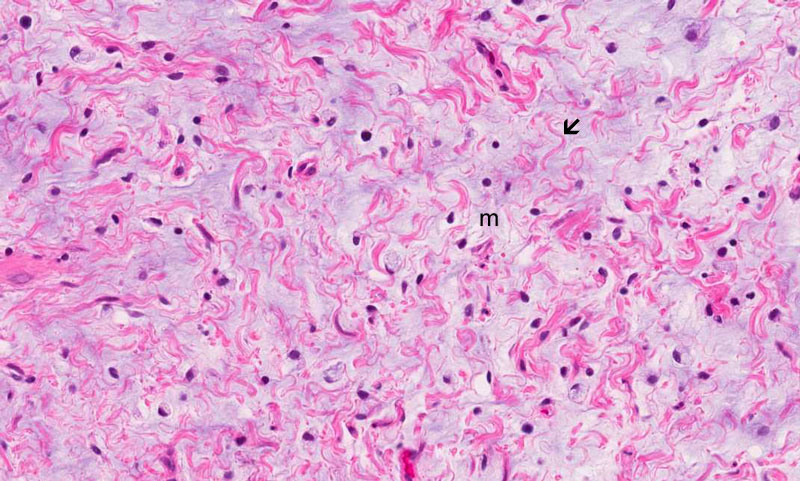

Hematoxylin & eosin

Area 2: The pale area is composed predominantly of a myxomatous background (m) and embedded within which are fine curvy collagen fibers (arrow). Note that the density of cells is almost identical in the eosinophilic areas and the pale areas.